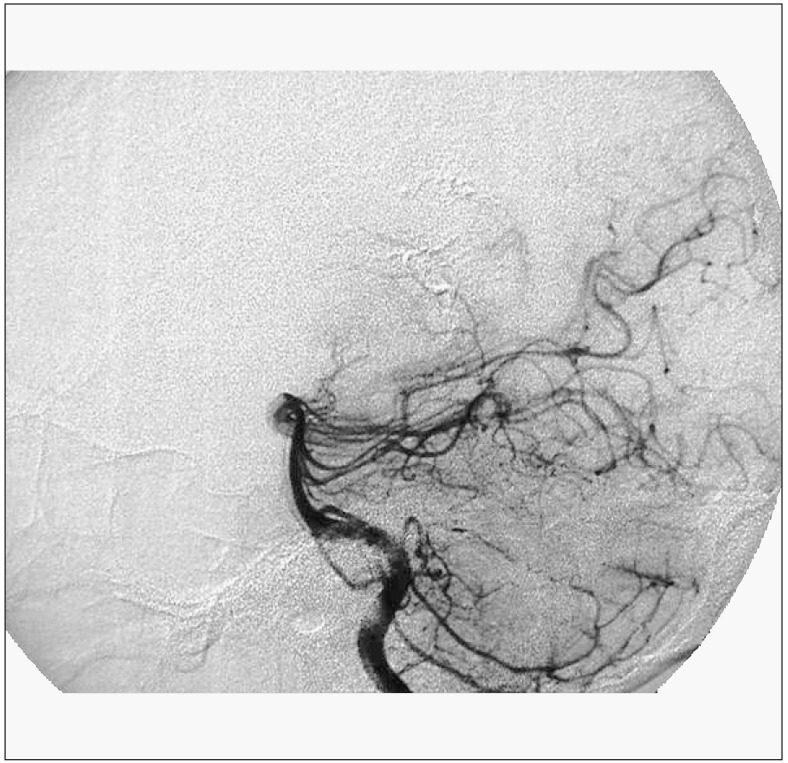

Figure 4.

male 23-years-old, hemorrhage in right ventricle. DSA shows a nidus of AVM in right ventricle (Right CCA injection AP View).

Figure 5.

DSA shows a nidus of AVM in right ventricle (Left DSA shows a nidus of AVM in right ventricle (Right CCA VA injection Lateral View). injection AP View).